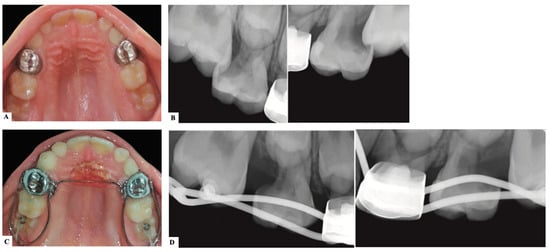

| Treatment Modalities | Severity of Impaction | Chair Side Time | Laboratory Work | Patient Discomfort | Cost | Treatment Duration |

|---|---|---|---|---|---|---|

| Elastic separator [35] | Mild to moderate | ↓ | ✕ | ↑ | ↓ | ↓ |

| Soft brass wire separator [37] | Mild to moderate | ↓ | ✕ | ↑ | ↓ | ↓ |

| Spring separator | Mild to moderate | ↓ | ✕ | ↑ | ↓ | ↓ |

| Humphrey appliance | Moderate to severe | ↑ | √ | ↓ | ↑ | ↓ |

| Halterman appliance [35] | Moderate to severe | ↑ | √ | ↓ | ↑ | ↓ |

| Croll’s appliance [4] | Moderate to severe | ↑ | √ | ↓ | ↑ | ↓ |

| Fixed edgewise appliance | Moderate to severe | ↑ | ✕ | ↓ | ↑ | ↓ |

| Surgical uprighting | Severe | ↑ | ✕ | ↑↑ | ↑↑ | ↑ |